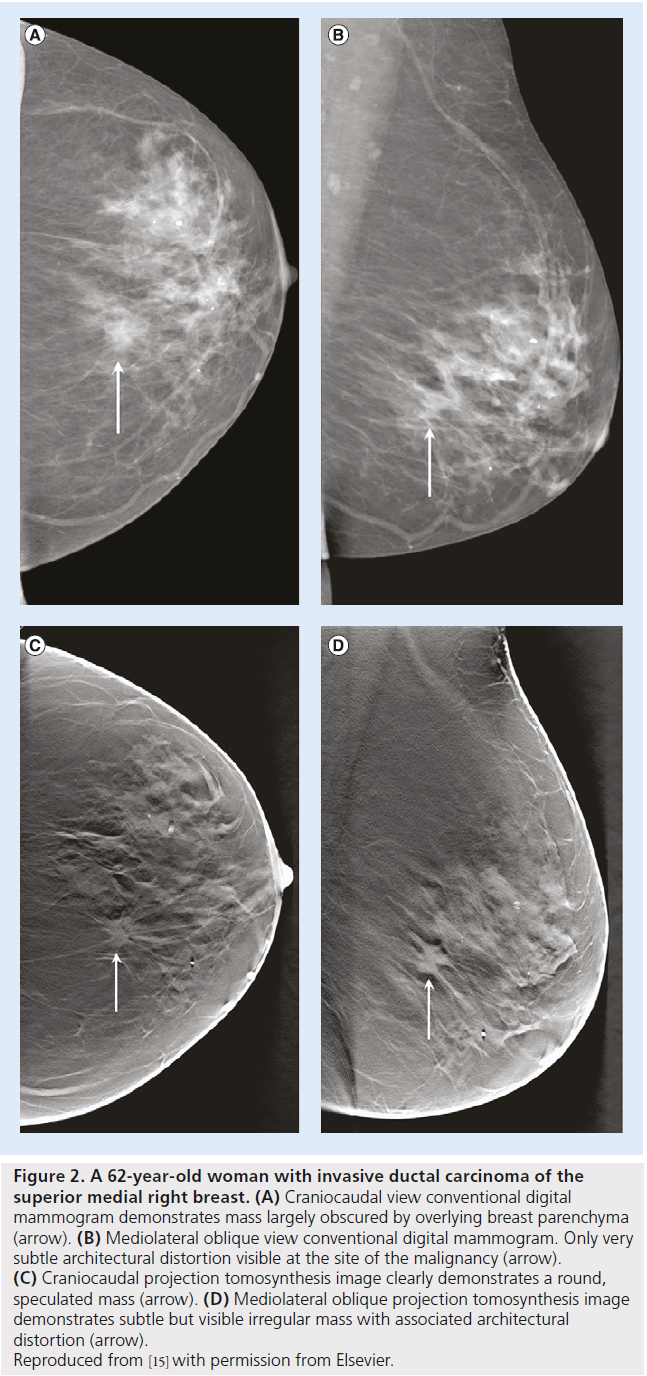

Various clinical studies have been devised to evaluate and assess the relative advantages or disadvantages of tomosynthesis to other technologies for screening and diagnosis. Figure 2 illustrates the potential advantage of two-view digital breast tomosynthesis with two-view digital mammography. In a 2007 study, Poplack et al. followedup 98 women with abnormal digital screening mammography with diagnostic film-screen mammography and tomosynthesis [51]. They reported an equivalent or superior image quality for tomosynthesis compared with diagnostic mammography in 89% of the cases and concluded that if tomosynthesis had also been used for screening, half of these cases would not have been recalled. It should, however, be noted that this study was not properly designed for such inference [52]. In 2008, Good et al. published a pilot study comparing full-field digital mammography, 11 low-dose projections acquired for the reconstruction of tomosynthesis images and the reconstructed digital breast tomosynthesis examinations of 30 subjects read by nine experts [53]. Although observer performance measures were not statistically significant, the authors reported great potentials for tomosynthesis-based breast imaging. In 2008, Andersson et al. published the results of a study conducted on symptomatic or recalled women in Sweden from 2006 to 2007. Their lesion visibility study, within a population of 40 cancers, concluded that cancer visibility in one-view tomosynthesis is superior to digital mammography. This indicated the potential of tomosynthesis to increase sensitivity [54]. In 2010, Teertsrtra et al. published the results of a study of 513 women with an abnormal screening mammogram or clinical symptoms in The Netherlands from 2006 to 2007 [55]. They found that the sensitivity of both techniques for the detection of breast cancer was 92.9%, and the specificity of mammography and tomosynthesis was 86.1 and 84.4%, respectively. They also concluded that tomosynthesis could be used as an additional technique to mammography in patients referred with an abnormal screening mammogram or with clinical symptoms. In 2010, Gennaro et al. published the results of a study of 200 women with at least one breast lesion discovered by mammography and/or ultrasound in Italy from 2007 to 2008 [56]. They concluded that the clinical performance of tomosynthesis in one view at the same total dose as standard screen-film mammography is not inferior to digital mammography in two views. In 2013, Skaane et al. published the results of a comparative study of digital mammography alone and digital mammography plus tomosynthesis in 12,631 women as part of the Oslo screening program from 2010 to 2011 [57]. They reported a 27% increase in the detection rate for invasive and in situ carcinoma cancers with digital mammography plus tomosynthesis, as well as a 15% decrease in false-positive rates. In 2013, Ciatto et al. published the results of investigating the effect of integrated mammography and tomosynthesis in population breast cancer screening [58]. This comparative study, STORM trial, recruited 7292 asymptomatic women aged 48 years or older who attended population-based breast cancer screening and reported that integrated mammography and tomosynthesis improves breast cancer detection and has the potential to reduce false-positive recalls.

Figure 2.A 62-year-old woman with invasive ductal carcinoma of the superior medial right breast. (A) Craniocaudal view conventional digital mammogram demonstrates mass largely obscured by overlying breast parenchyma (arrow). (B) Mediolateral oblique view conventional digital mammogram. Only very subtle architectural distortion visible at the site of the malignancy (arrow). (C) Craniocaudal projection tomosynthesis image clearly demonstrates a round, speculated mass (arrow). (D) Mediolateral oblique projection tomosynthesis image demonstrates subtle but visible irregular mass with associated architectural distortion (arrow). Reproduced from [15] with permission from Elsevier.